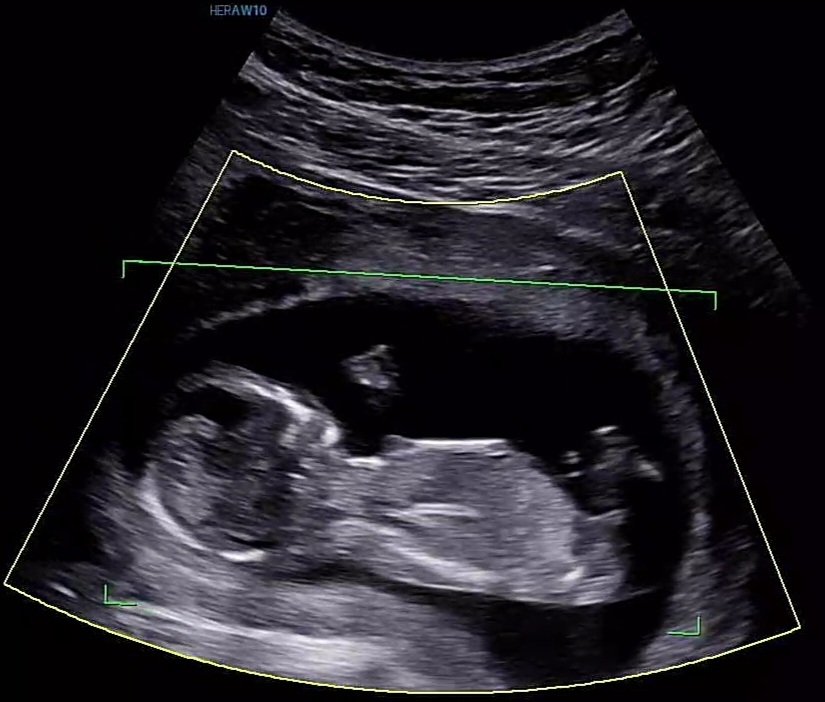

엇.....!! 저 삐쭉한 부분이 생식기 쪽이라면 저도 아들로 보이는데욧...?!

반신반의로 올려보는..ㅎㅎ

어른들은 아들을 쪼끔 더 원하시는 것 같지만 저희 부부는 첫째만큼은 꼭!!!!! 딸이었으면 하는..ㅎㅎ 먹고싶은 음식 종류만 보면 딸같은데 우리 공룡이 공주일까요!?!?!?!?ㅎㅎ

아들같아요😊